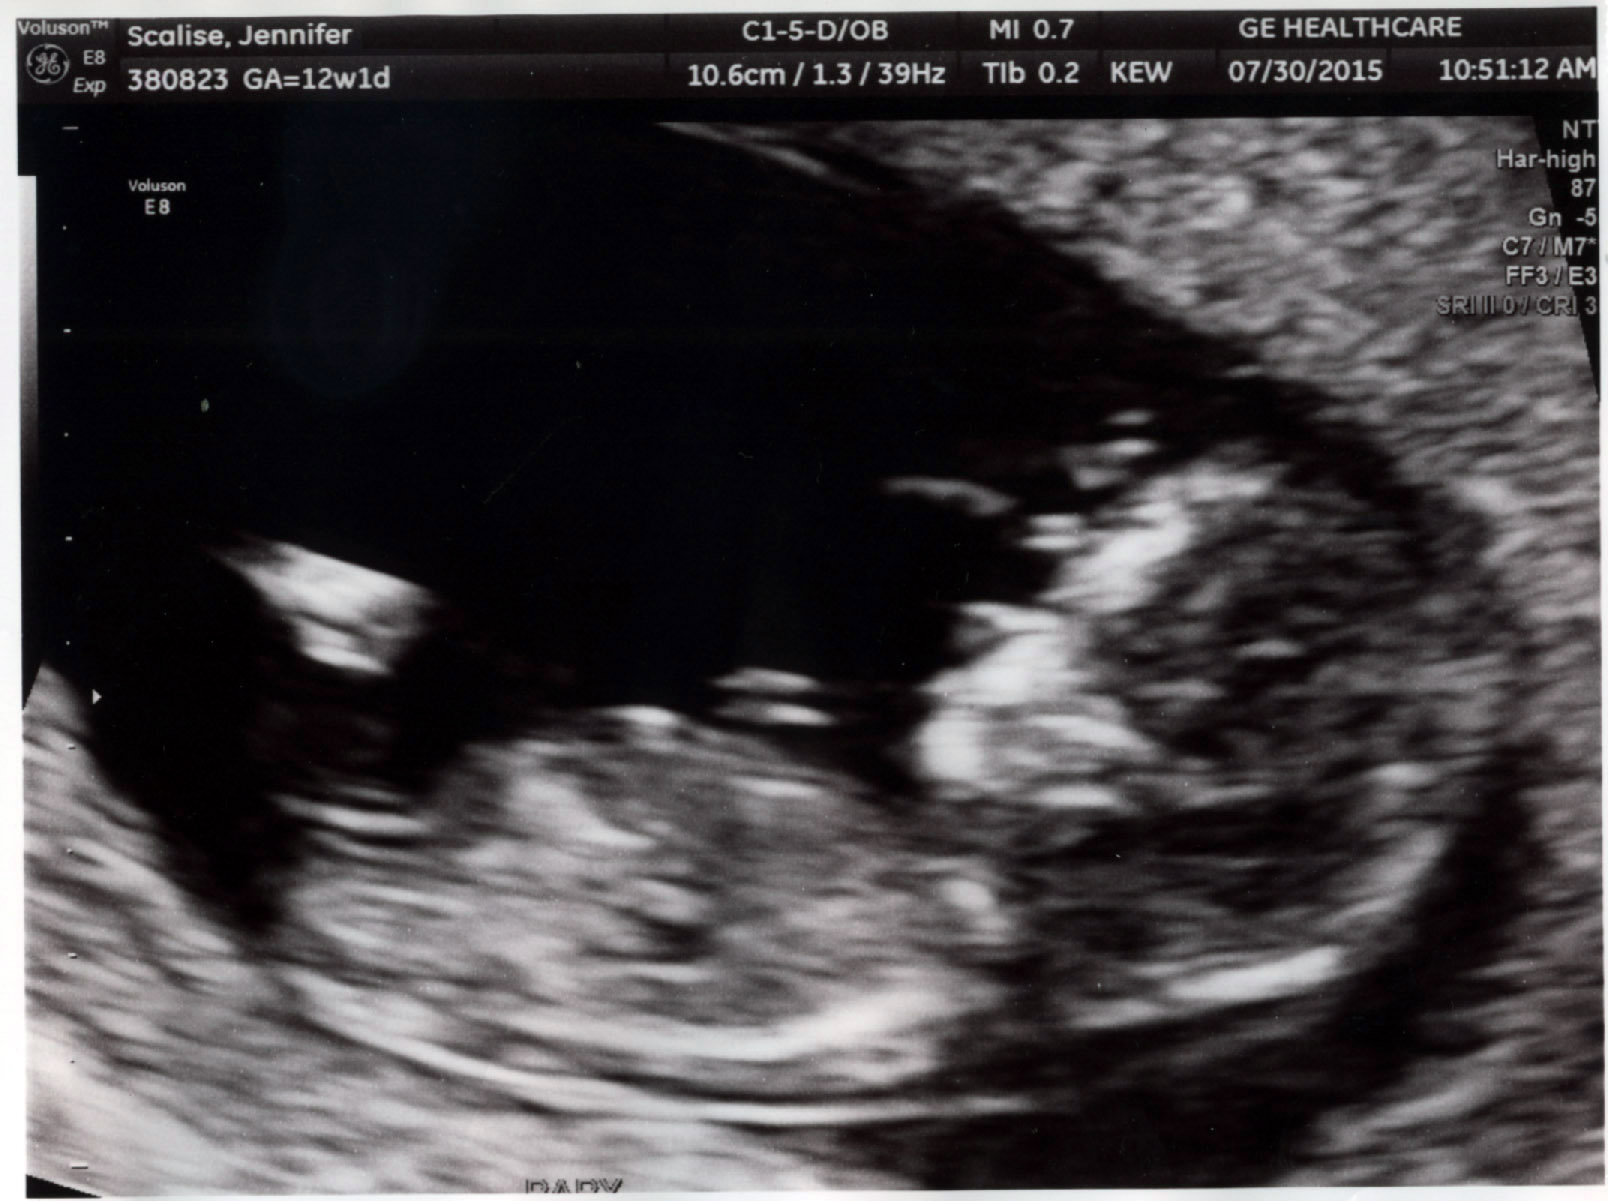

Just wondering if anyone has any thoughts based on this image.

girl

I just want to update that after 2 boys, this baby is a healthy baby GIRL!!!